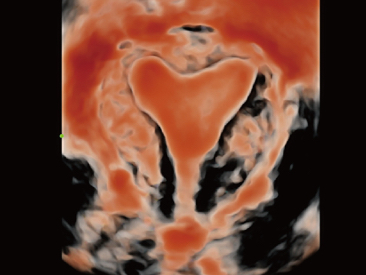

Sinds de oprichting van het bedrijf is Mindray voortdurend op zoek naar nieuwe manieren om het diagnostisch vertrouwen te vergroten. Resona 7 wordt aangestuurd door de meest revolutionaire ZONE Sonography?-technologie. Zijn nieuwe ZST+-tilt de kwaliteit van ultrasoundbeeldvorming naar een hoger niveau door middel van zoneacquisitie en kanaalgegevensverwerking.

Naast de hoogwaardige beeldvormingskwaliteit verbetert de Resona 7 tevens de klinische onderzoeksmogelijkheden met de revolutionaire V Flow voor vasculaire hemodynamische evaluatie, en de intelligentste vlakacquisitie van een 3D-gegevenssets voor de diagnose van het foetale, centrale zenuwstelsel. Met zijn combinatie van de meest intu?tieve, op vingerbewegingen gebaseerde multi-aanrakingsbediening en alle essenti?le klinische functies loopt de Resona 7 voorop in de nieuwe golven van ultrasoundinnovatie.